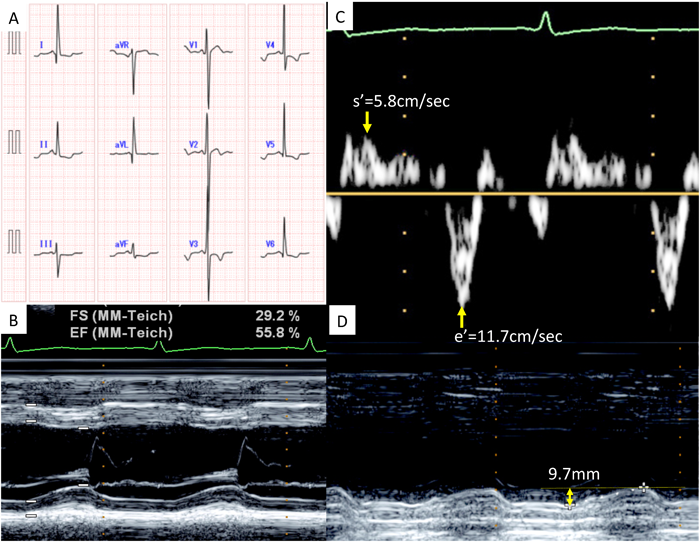

Fig. 13は,学校心電図異常で紹介された左室緻密化障害(15歳男児)の1例である.左室内径短縮率は29%で,軽度低下を認めた.左室長軸方向のTDIではs′とe′共に軽度低下していた.MAPSEは著明に低下しており,心筋障害が強く示唆された.

Pediatric Cardiology and Cardiac Surgery 32(2): 70-77 (2016)

Fig. 13 MAPSE in a patient with left ventricular noncompaction

A 15-year-old boy was referred to our hospital because of ECG abnormality found during heart screening for schoolchildren. A: ECG shows ST–T change in the left precordial leads. B: Shortening fraction of the left ventricle is marginally decreased to 29%. C: Tissue Doppler imaging recorded from the lateral mitral valve annulus shows decreased velocity of systolic (s′) and early diastolic waves (e′). D: MAPSE recorded by M-mode is significantly decreased to 9.7 mm, indicating a distinct abnormality of the longitudinal systolic function of the left ventricle. MAPSE=mitral annular plane systolic excursion; ECG=electrocardiogram.